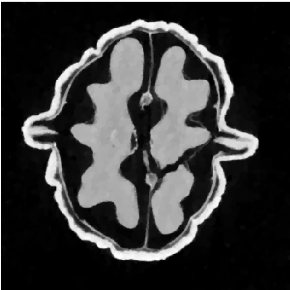

4.1 Experiment 1 (Walnut / TV)

Refer to caption

(a) Under-reg (α=1010\alpha=10^{-10})

(b) Target (α2.3e-6\alpha\approx 2.3\text{e-}6)

(c) Over-reg (α2.3e-4\alpha\approx 2.3\text{e-}4)

(d) SSIM over α\alpha

Fig. 2: Walnut / TV. (a) Initial noise-dominated state. (b) The converged result at target SSIM 0.95. (c) Over-regularized reference showing loss of detail. (d) The recorded monotonic SSIM vs. α\alpha curve. The controller halts in the target band.

Figure 2 illustrates the controller response on the Walnut dataset using TV regularization. The initial negligible regularization (α0=1010\alpha_{0}=10^{-10}) created a noisy reconstruction (Fig. 2(a)). The low inter-grid SSIM (S0.53S\approx 0.53) generated a large control error, which drove a progressive increase in α\alpha. SSIM rose monotonically to reach the user-defined target Sref=0.95S_{\mathrm{ref}}=0.95. The corresponding reconstruction (Fig. 2(b)) suppressed noise effectively and preserved sharp boundaries of both the shell and internal septa. Once stable convergence was achieved, the controller terminated automatically.

We then set a large α2.3×104\alpha\approx 2.3\times 10^{-4} to generate an over-regularized reconstruction (Fig. 2(c)). This suffered from pronounced loss of structural detail, illustrating that high similarity alone does guarantee a desirable result. The SSIM trajectory in Fig. 2(d) confirms the monotonicity of the similarity function S(α)S(\alpha) defined in (3). Using the domain-specific knowledge, the controller halts the process on the rising edge of the curve to avoid trivial over-regularization.